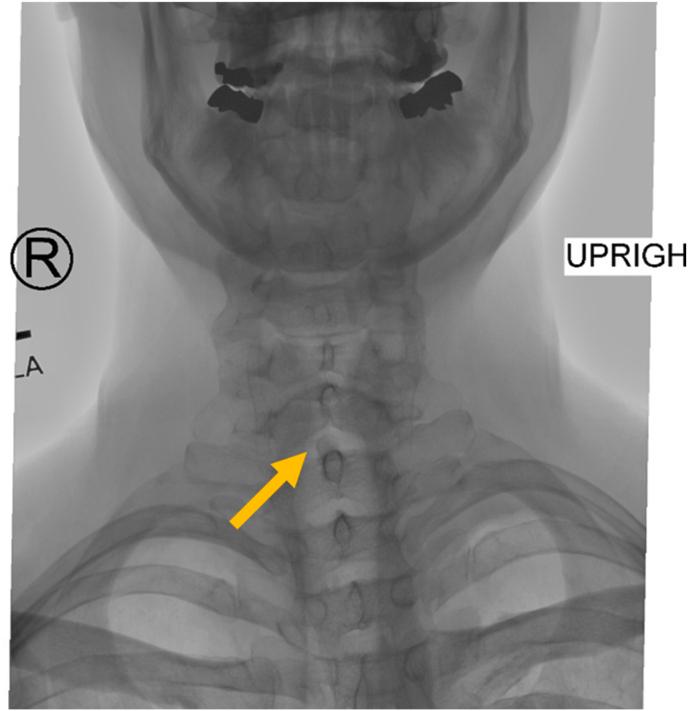

Posterior internal vertebral venous plexus, the "Black Ice" of epidural hematoma: A letter to the editor.

Posterior internal vertebral venous plexus, the "Black Ice" of epidural hematoma: A letter to the editor.椎内静脉后丛,硬膜外血肿的“黑冰”:致编辑的一封信

Fulminant Cervical Epidural Hematomas: Why Do They Happen, How Can We Minimize Their Occurrence, and What Can We Do When They Do Occur? A Perspective.

Spinal Epidural Hematoma after Interlaminar Cervical Epidural Steroid Injection.

Cervical epidural hematoma following interlaminar epidural steroid injection via the contralateral oblique view in patient taking omega-3 fatty acids.患者服用欧米伽-3 脂肪酸后,从对侧斜位行椎间孔硬膜外类固醇注射导致颈椎硬膜外血肿。